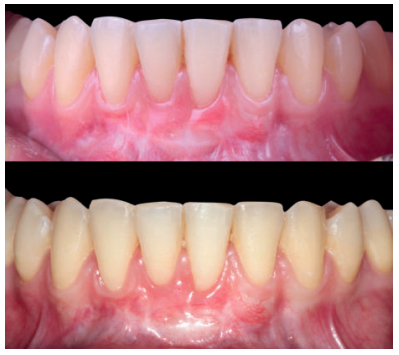

Se realizó control a la semana de la intervención (Figura 4) y tras 15 días se retiró la sutura, observando la revascularización del injerto y la epitelización del área cruenta apical al sobre (Figura 5). Se realizó seguimiento al mes (Figura 6), a los 3 meses (Figura 7) y al año y medio del procedimiento (Figura 8).

El control a la semana (Figura 13) presentaba inflamación moderada y a las 2 semanas (Figura 14) se retiraron los puntos de sutura. La paciente acudió a los 4 meses (Figura 15) y al año (Figura 16) a visitas de revisión, donde se apreció una buena banda de tejido queratinizado y una pequeña cicatriz.